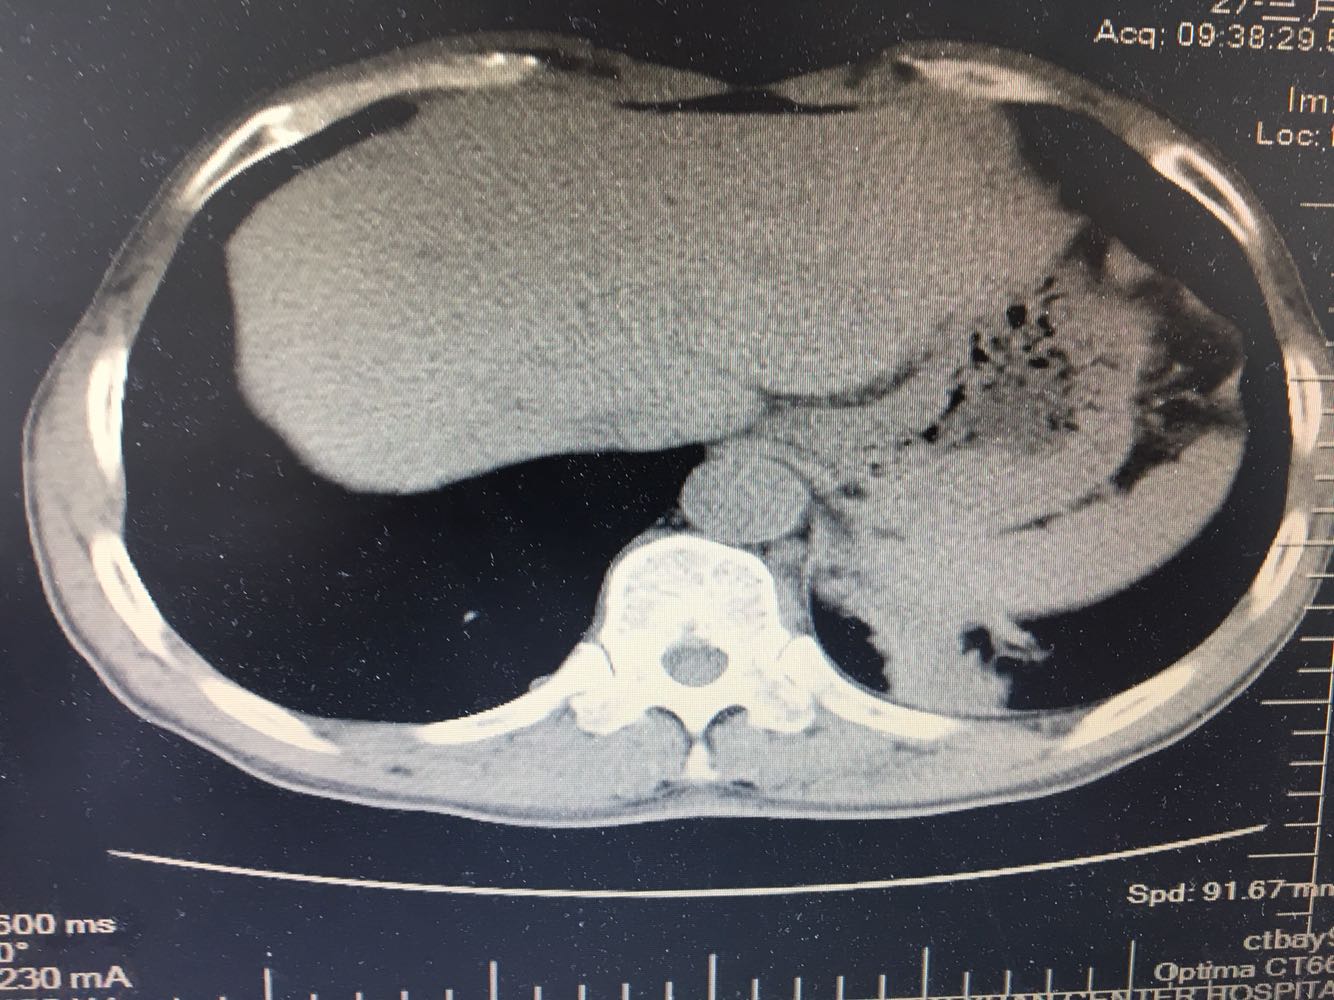

男,63岁,咳嗽1个月入院,患者自述1个月前无诱因咳嗽,阵发性干咳,无痰,时有血丝,无发热,左胸痛,活动后气短,静滴头孢13天无好转,门诊查肺CT后以 肺占位收入我科,病来饮食睡眠可,体重明显下降。既往疝气术后1年,吸烟史30年,每日1包。

左肺癌

左肺中央型肺癌,是否可以手术,还是化疗,放疗,靶向治疗?